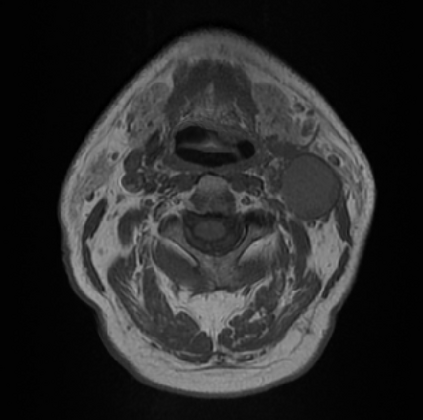

Organ at risk (OAR) segmentation is a critical process in radiotherapy treatment planning such as head and neck tumors. Nevertheless, in clinical practice, radiation oncologists predominantly perform OAR segmentations manually on CT scans. This manual process is highly time-consuming and expensive, limiting the number of patients who can receive timely radiotherapy. Additionally, CT scans offer lower soft-tissue contrast compared to MRI. Despite MRI providing superior soft-tissue visualization, its time-consuming nature makes it infeasible for real-time treatment planning. To address these challenges, we propose a method called SegReg, which utilizes Elastic Symmetric Normalization for registering MRI to perform OAR segmentation. SegReg outperforms the CT-only baseline by 16.78% in mDSC and 18.77% in mIoU, showing that it effectively combines the geometric accuracy of CT with the superior soft-tissue contrast of MRI, making accurate automated OAR segmentation for clinical practice become possible. See project website https://steve-zeyu-zhang.github.io/SegReg